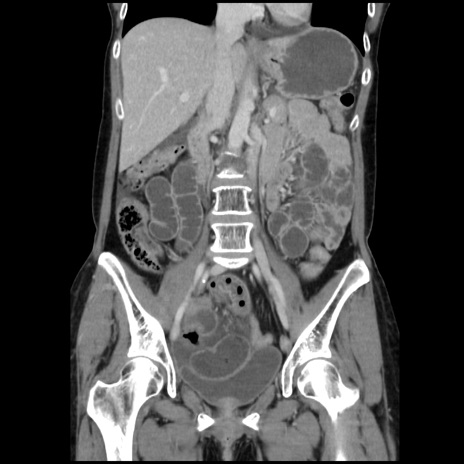

症例32(冠状断像)

【症例】40歳代 女性

【主訴】上腹部痛、嘔気・嘔吐

【現病歴】約9時間前頃から急に上腹部痛、嘔気、嘔吐が出現。改善しないため救急要請。

【既往歴】子宮頚癌(広汎子宮全摘術、放射線療法)、腸閉塞

【身体所見】腹部:平坦、軟、腸雑音亢進、上腹部を中心に腹部全体に圧痛あり。

【データ】WBC 8400、CRP 0.03